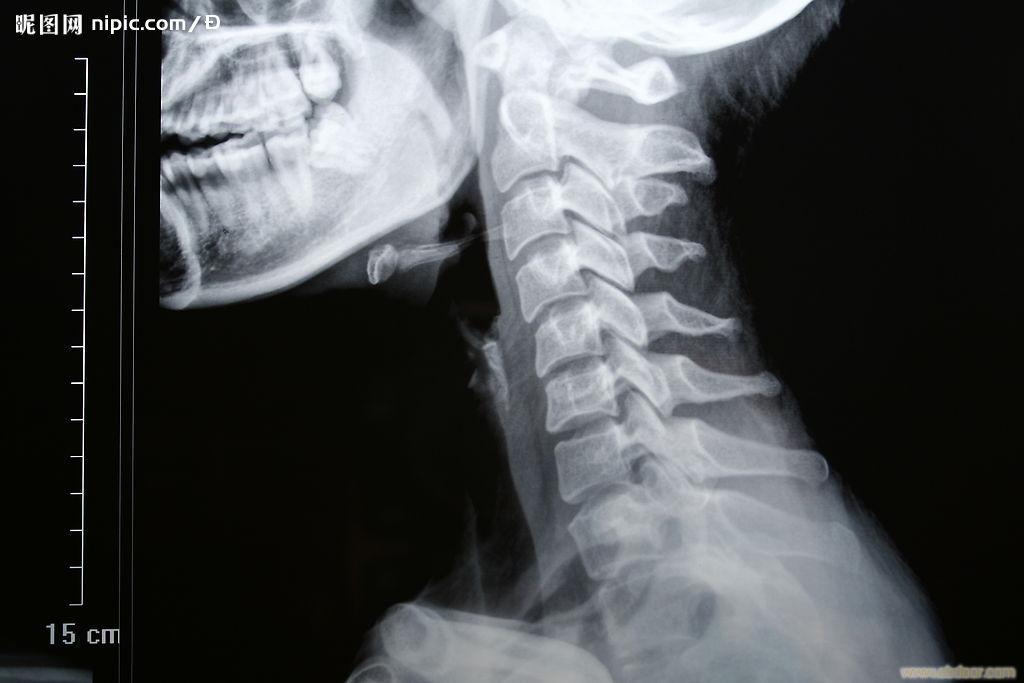

答:因为脖子里的“骨头”,与“神经”是紧挨着的。(见下图)

现代科学研究发现,颈椎病的发病机理是: (1)颈部“队列”变形,刺激或压迫到了神经(或血管); (2)被挤压的这条神经肿胀、发炎; (3)这条发炎的神经所管理的肌肉产生痉挛并疼痛,或这条发炎的神经所管理的器官的功能失常。 可见,上述的“因果关系”是:

颈椎“队列”变形——→神经受压并发炎——→肌肉“发紧”并酸痛或器官功能失常。 所以,队列变形是“因”,神经发炎是“果”,其他部位症状(如:肌肉酸痛)是“果”引起的“果”。